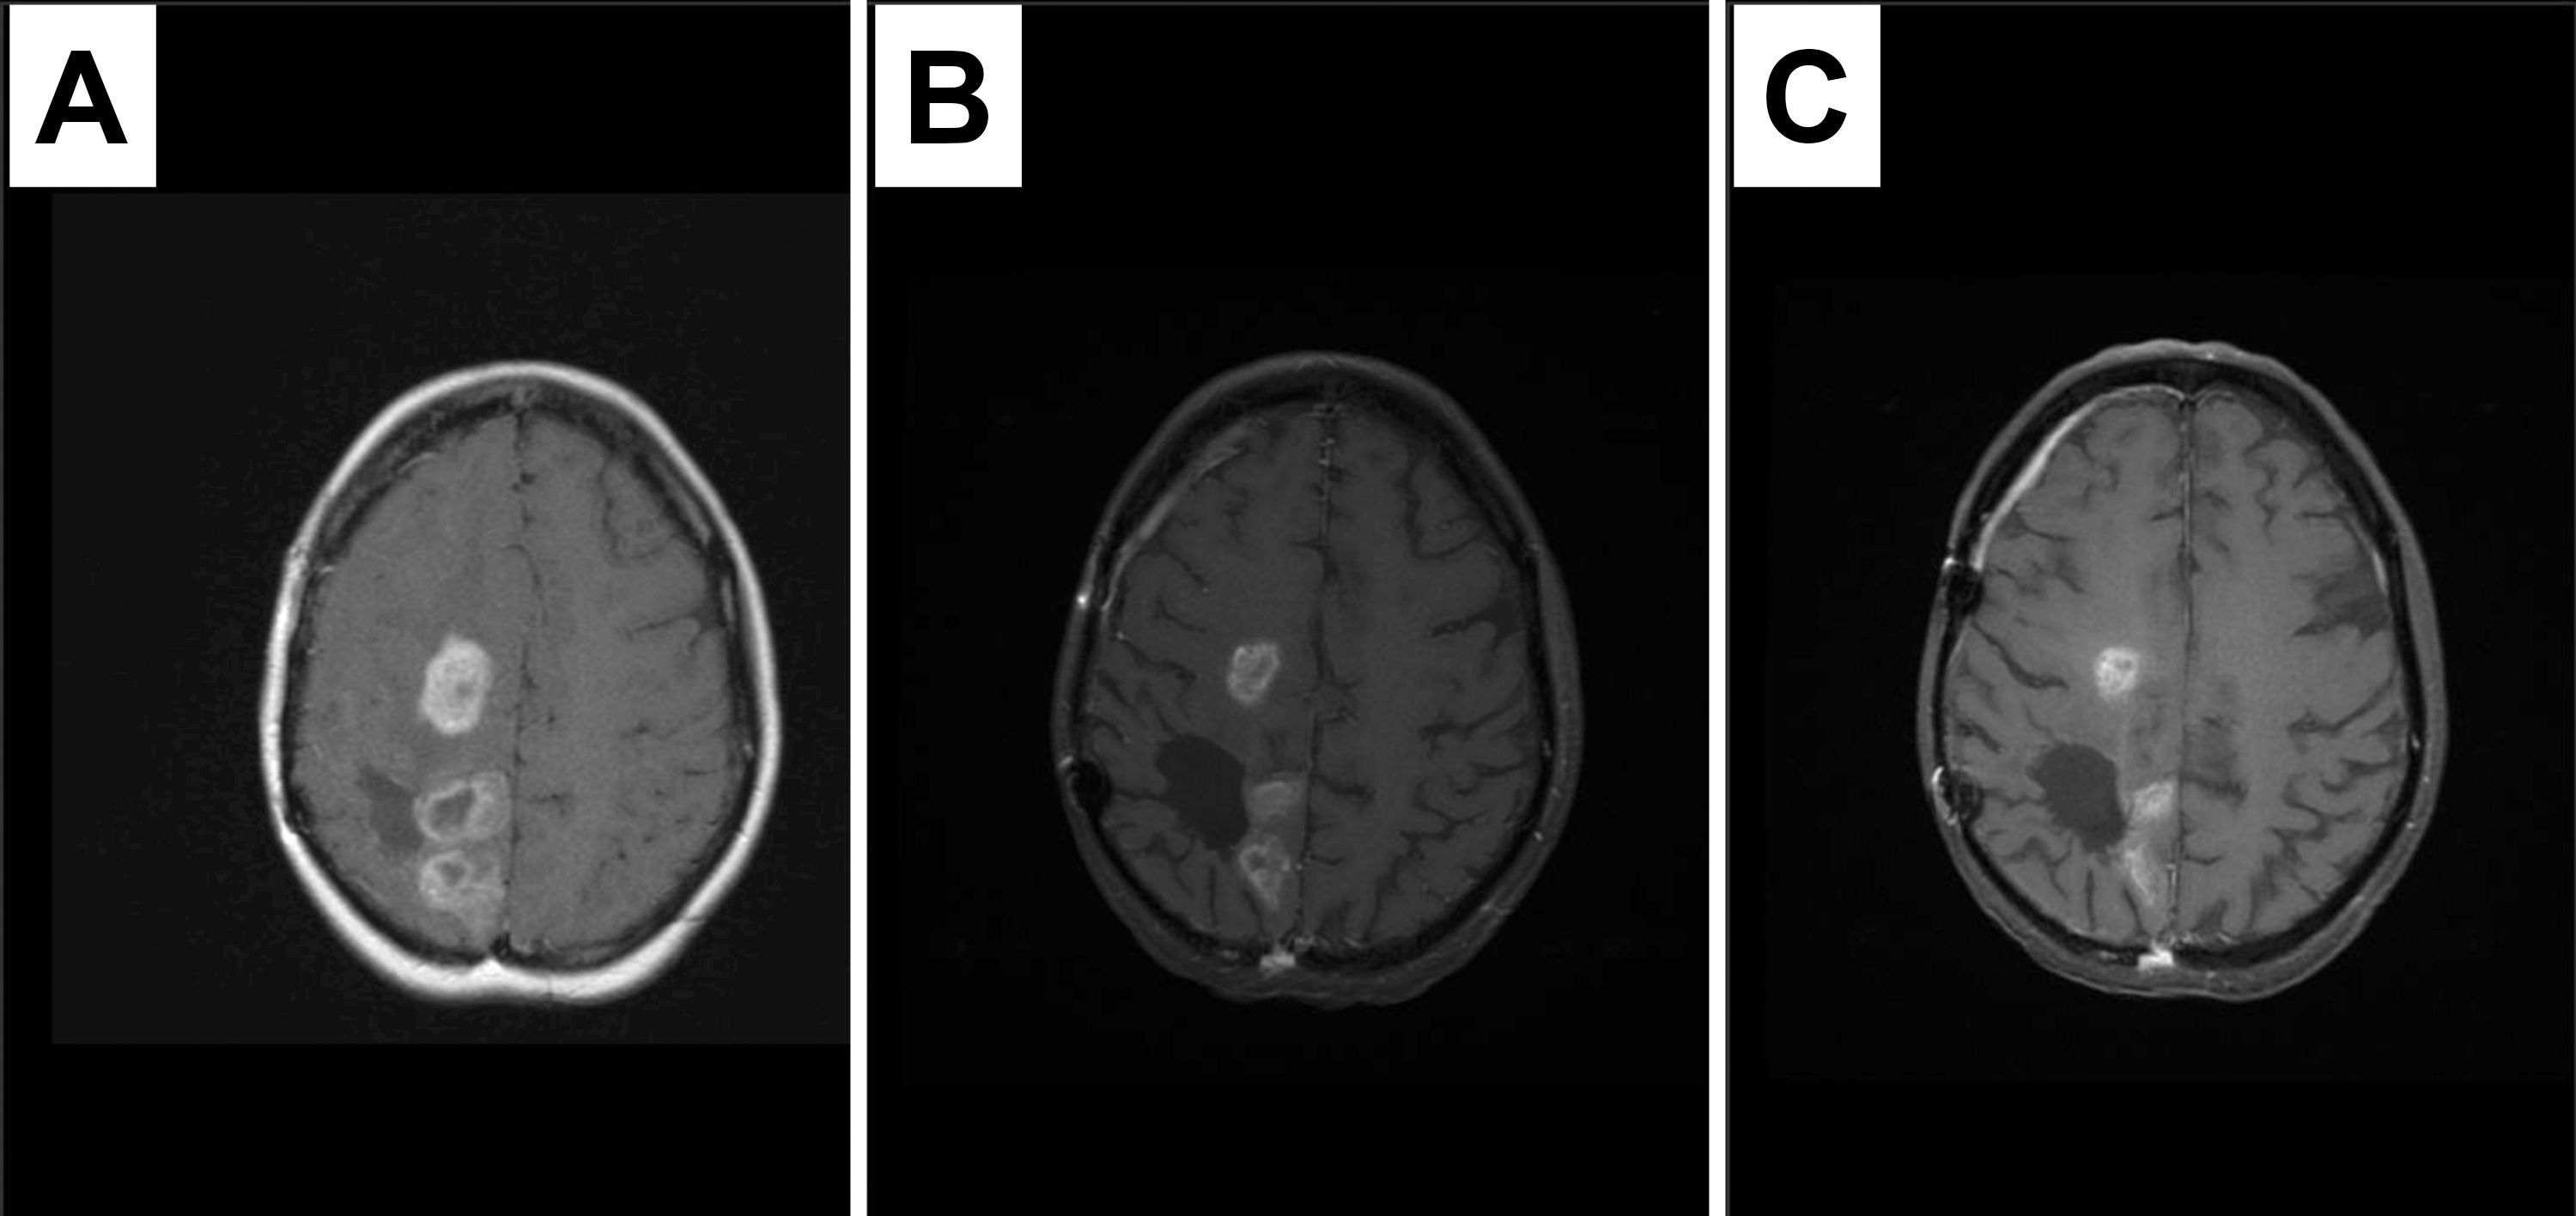

therapy for 9 months until disease progression. Subject 3 experienced initial

response to combination study treatment which was sustained for

Fig. 3.Response to therapy containing dasatinib in a recurrent tumor with PDGFRA immunopositivity and amplification. MRI images at study enrollment (A), 3 months later demonstrating response (B) sustained at six months (C). Patient remained on therapy for 9 months until disease progression.